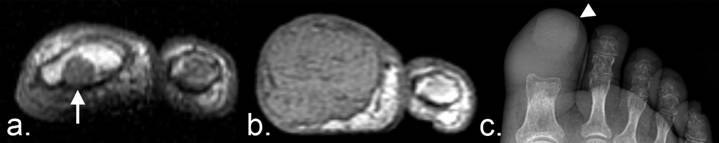

RECIST 1.1 designates numerous lesions as unmeasurable. These include small tumors (nodules with a short-axis dimension < 10 mm), leptomeningeal disease, lymphangitic spread, inflammatory breast disease, pericardial/pleural effusions, palpable abdominal masses/organomegaly not reproducible on imaging studies, lesions surrounded by postradiation scar tissue, and bone metastases without soft tissue masses measuring ≥ 10 mm (the large majority of bone metastases). While no focus of unmeasurable disease can be used as a target lesion, the progression of such tumors can have an effect on the RECIST response assessment under the designation of unequivocal progression of nontarget lesions. In general, progression of nontarget lesions is to be estimated as a 20% increase in the sum of the greatest tumor diameters, which is calculated to be a 73% increase in volume, by the authors of the RECIST criteria (11). Therefore, frank progression of bone metastases on any imaging modality can contribute to the classification of overall patient response through the designation of unequivocal progression (Fig. 3).

Figure 3

Unequivocal progression of unmeasurable disease according to the RECIST 1.1 criteria. (a)T1-weighted axial MRI of a patient with renal cell carcinoma demonstrates a small metastasis in the marrow cavity of the distal phalanx of the left great toe (arrow). Bone disease without a soft tissue mass ≥ 10 mm is considered unmeasurable disease under RECIST 1.1. (b) Eight months later, the metastasis has markedly enlarged, representing unequivocal progression of unmeasurable disease. (c) A frontal radiograph of the foot demonstrates complete cortical lysis of the distal phalanx. The toenail is evident (arrowhead). Periarticular osteopenia is likely secondary to disuse.